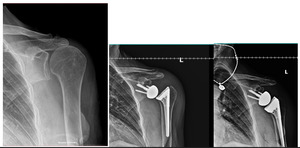

The first patient is a 78-year-old female who initially presented with severe rotator cuff arthropathy following a previous rotator cuff repair. The patient underwent a reverse shoulder arthroplasty procedure and subsequently sustained an atraumatic dislocation one month postoperatively with an anterosuperior translation of the humeral component relative to the glenoid. A revision procedure was then performed for the patient, which involved upsizing the tray to a +8 with a +4 semi-constrained polyethylene liner and increasing the glenosphere size from 32+4 mm to 36+4 mm. As per the described technique, a glenoid-anchor cerclage was also placed to provide additional stability to the construct. One year postoperatively, the patient remains stable with no evidence of complications associated with the glenoid-anchor cerclage. The patient has a forward elevation of 120 degrees and an external rotation of 10 degrees, with an American Shoulder and Elbow Score (ASES) and Single Assessment Numerical Evaluation (SANE) score of 60. The patient has also expressed a high level of satisfaction with the surgery. She has noticed some improvement over the past six months and is optimistic about further progress in the coming year. Her primary goal is to regain enough mobility to play golf again. [Figure 3]

Regarding range of motion measurements, the patient has 90 degrees of forward elevation, 40 degrees of external rotation, and the ability to internally rotate to the sacrum. The patient also presents free of complications associated with the glenoid-anchor cerclage. [Figure 4]